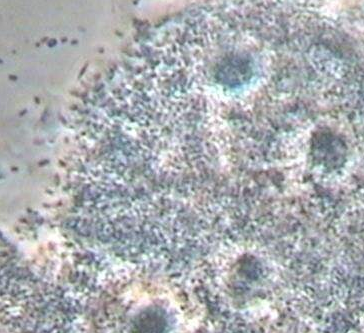

线索细胞是加德纳杆菌或小杆菌感染正常的鳞状上皮细胞,使正常的鳞状上皮细胞形状发生改变,如边缘不齐整、不光滑、清晰度不高等。其为阴道脱落鳞状上皮细胞上黏附大量加特纳杆菌等厌氧菌的一种形状表现。当女性分泌物中出现大量线索细胞时,一般预示患了细菌性阴道病。当然也要结合别的几项至关重要指标值来确诊,一般是pH值、胺试验及分泌物增多性状等指标值。